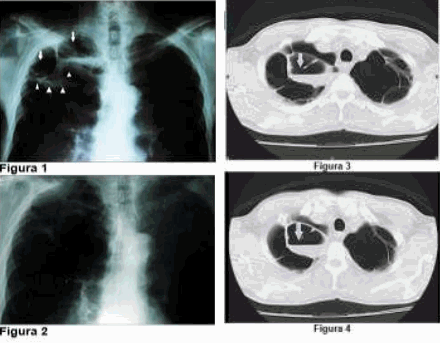

La figura 1 muestra la radiografía de tórax, vista posteroanterior (PA), realizada el día 5 de octubre de 2013, en la que se observa un marcado aumento de la radio transparencia pulmonar bilateral, signo evidente de enfisema pulmonar, el vértice pulmonar derecho presenta dos bullas (flechas), rodeadas por una opacidad heterogénea que las delimita, en relación con tractos fibróticos (cabezas de flecha). La bulla paramediastinal muestra un nivel hidroaéreo bajo, que pudiera estar en relación con bulla infectada (cabezas de flechas).

El paciente fue tratado con cefalexina vía oral, cápsula de 500 mg cada 6 horas más metronidazol vía oral 250 mg cada 6 horas durante 10 días, después de lo cual desaparecieron las manifestaciones clínicas, así como el infiltrado pulmonar heterogéneo y el nivel hidroaéreo de la radiografía de tórax descritos previamente (figura 2).

En cortes axiales de la tomografía computadorizada simple de tórax con ventana de parénquima pulmonar, realizada durante el período de tratamiento con antibióticos, se observa a nivel de ambos vértices pulmonares, ausencia de parénquima y múltiples bullas enfisematosas; constatándose en la bulla paramediastinal derecha la presencia de nivel hidroaéreo en su interior, ya diagnosticada en la radiografía de tórax (observar flechas en la figura 3 y en la figura 4).